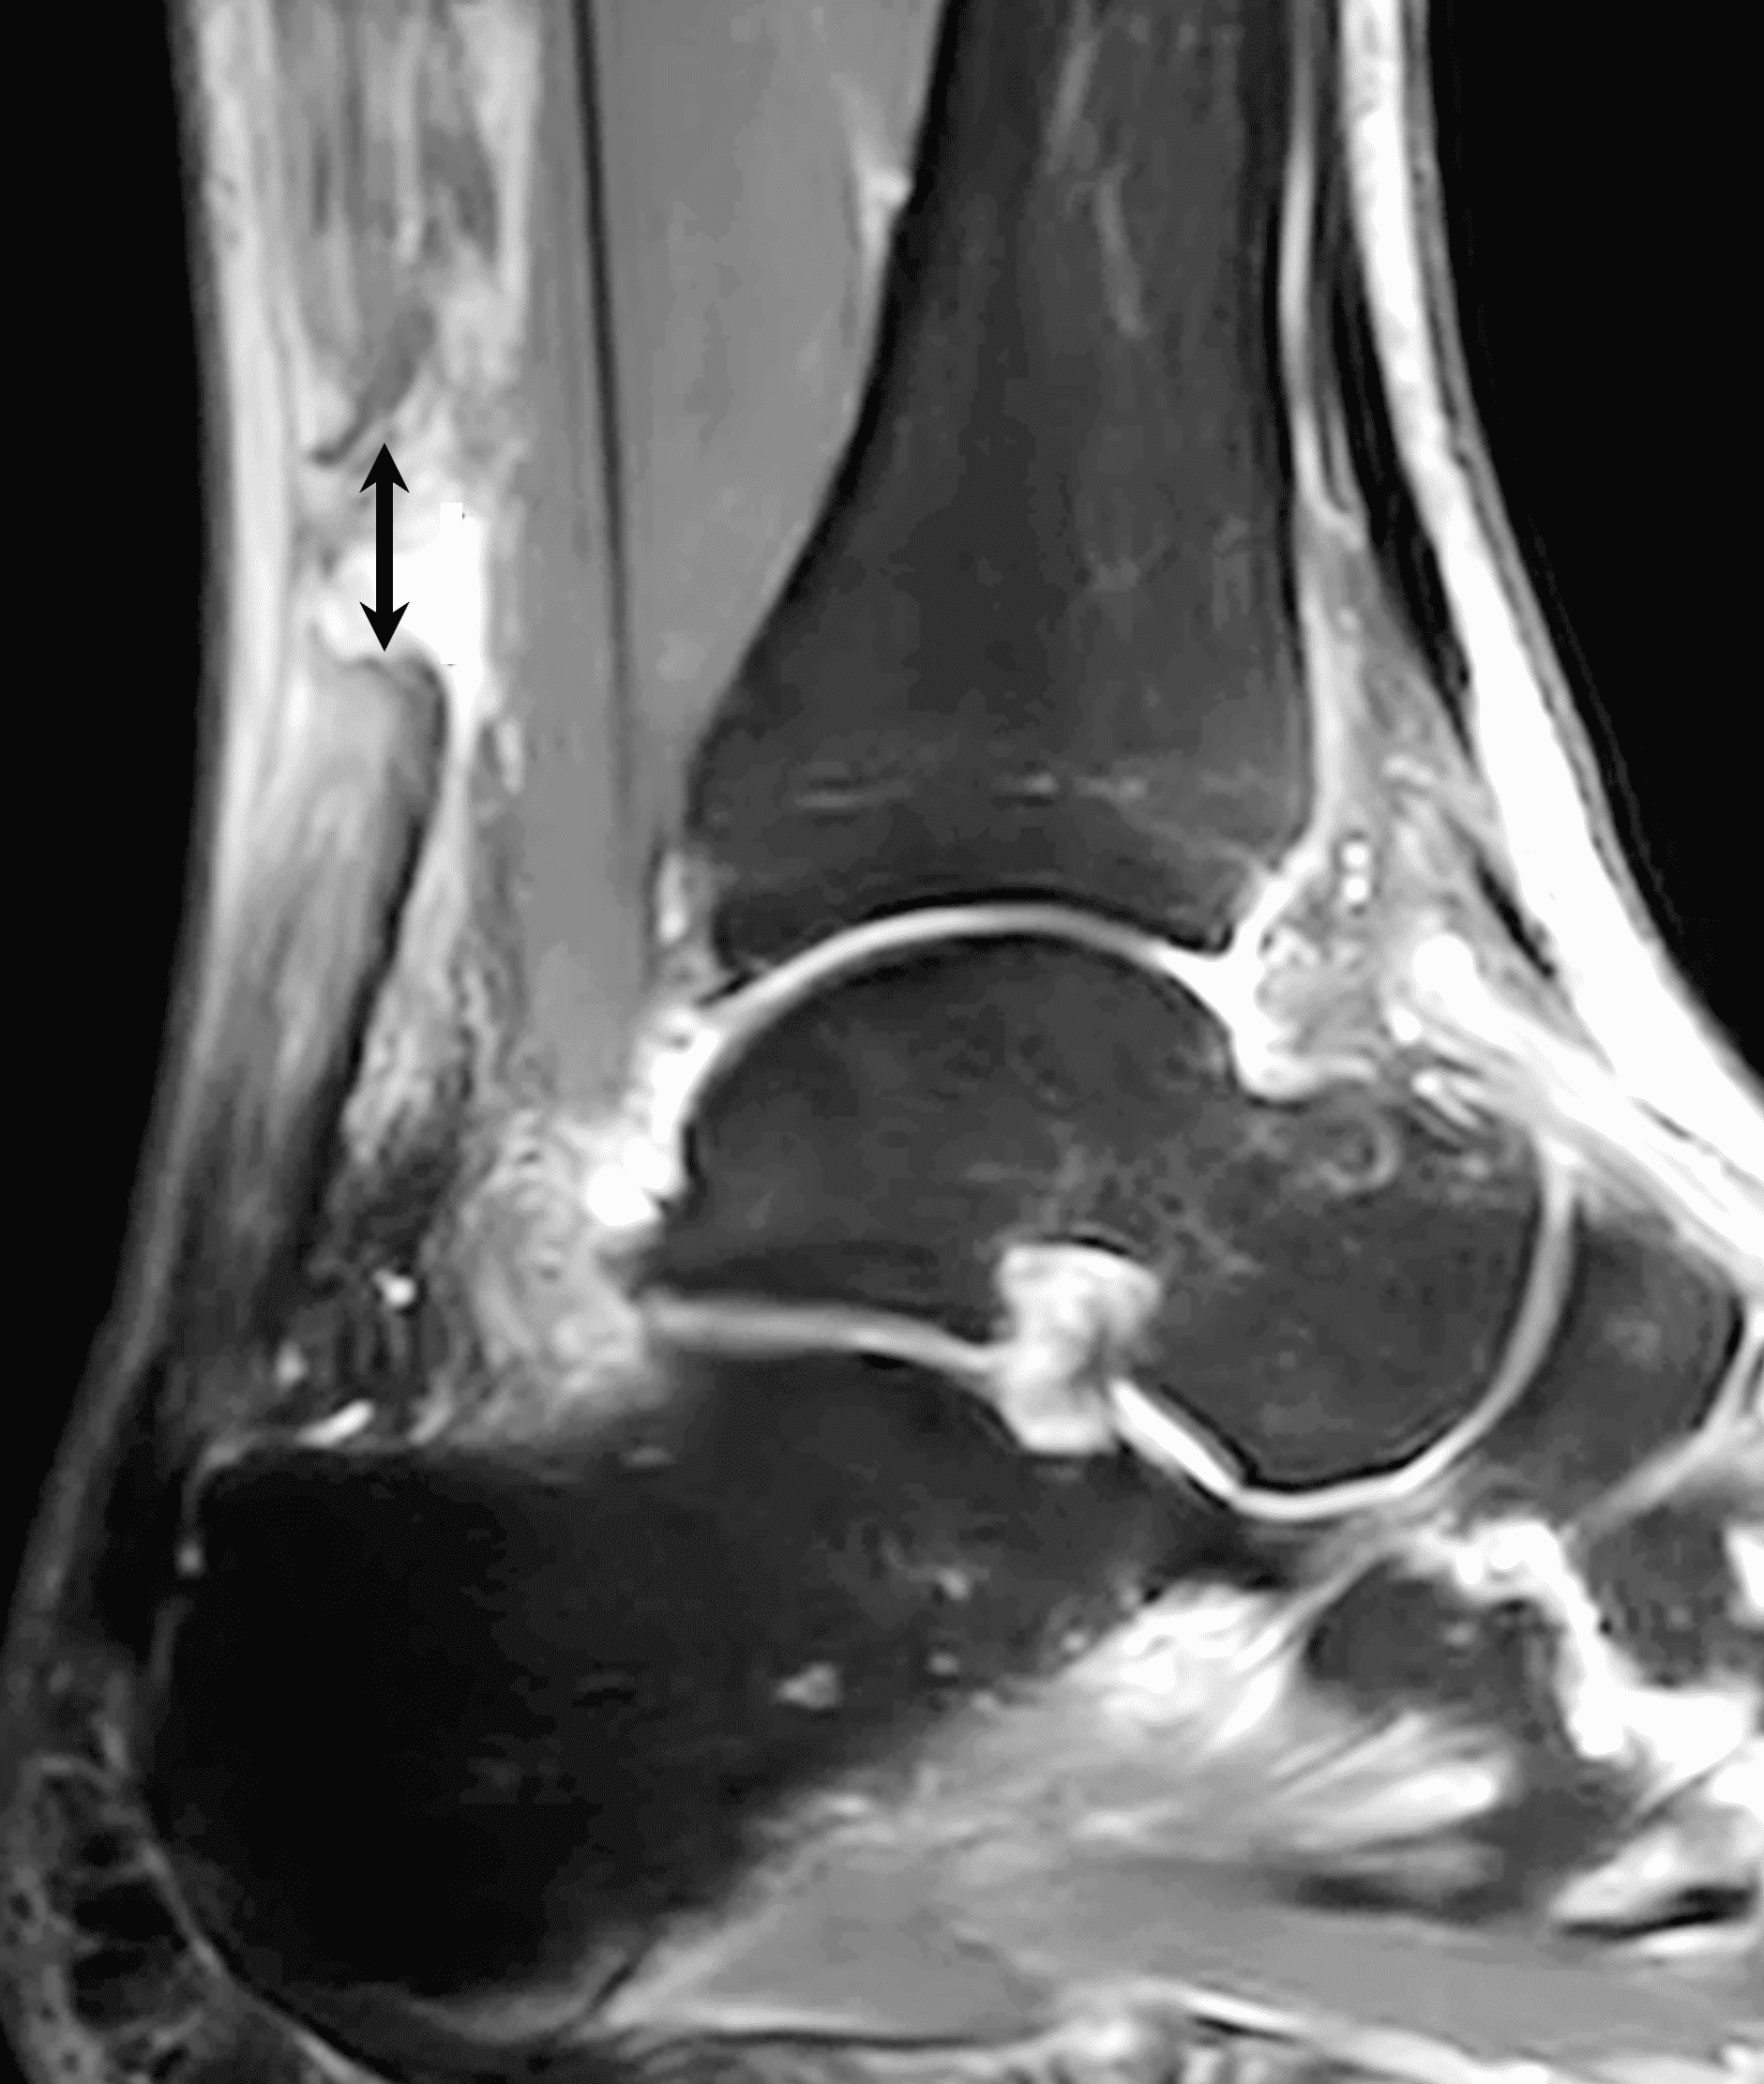

A 22 year-old male college football player presents with a “pop” and pain posterior to the right ankle during practice 1 week prior. He is unable to bear weight. Lateral radiograph (1A), sagittal fat-suppressed T2-weighted (1B), sagittal T1-weighted (1C), and transverse fat-suppressed T2-weighted images are provided. What is your diagnosis? What MRI findings affect clinical management decisions?

Figure 2: Complete Achilles tendon rupture. (2A) The lateral radiograph shows a thick and indistinct proximal Achilles tendon contour (arrows). (2B) A fat-suppressed T2-weighted image shows complete rupture of the tendon with a fluid-filled gap (yellow arrow) measuring 1.5 cm in length, located 10 cm cranial to the tendon insertion (blue arrow) and just distal to the edematous myotendinous junction (red arrow). The tear is superimposed on diffuse tendinosis. (2C) A sagittal T1-weighted image confirms the diffuse tendinosis. Fluid extends anteriorly into Kager’s fat pad (arrow) suggesting disruption of the anterior paratenon. (2D) A transverse fat-suppressed T2-weighted image through the proximal tendon shows no intact fibers (arrow), confirming the full-thickness rupture.

Acute, complete Achilles tendon rupture just distal to the myotendinous junction, superimposed on diffuse tendinosis.